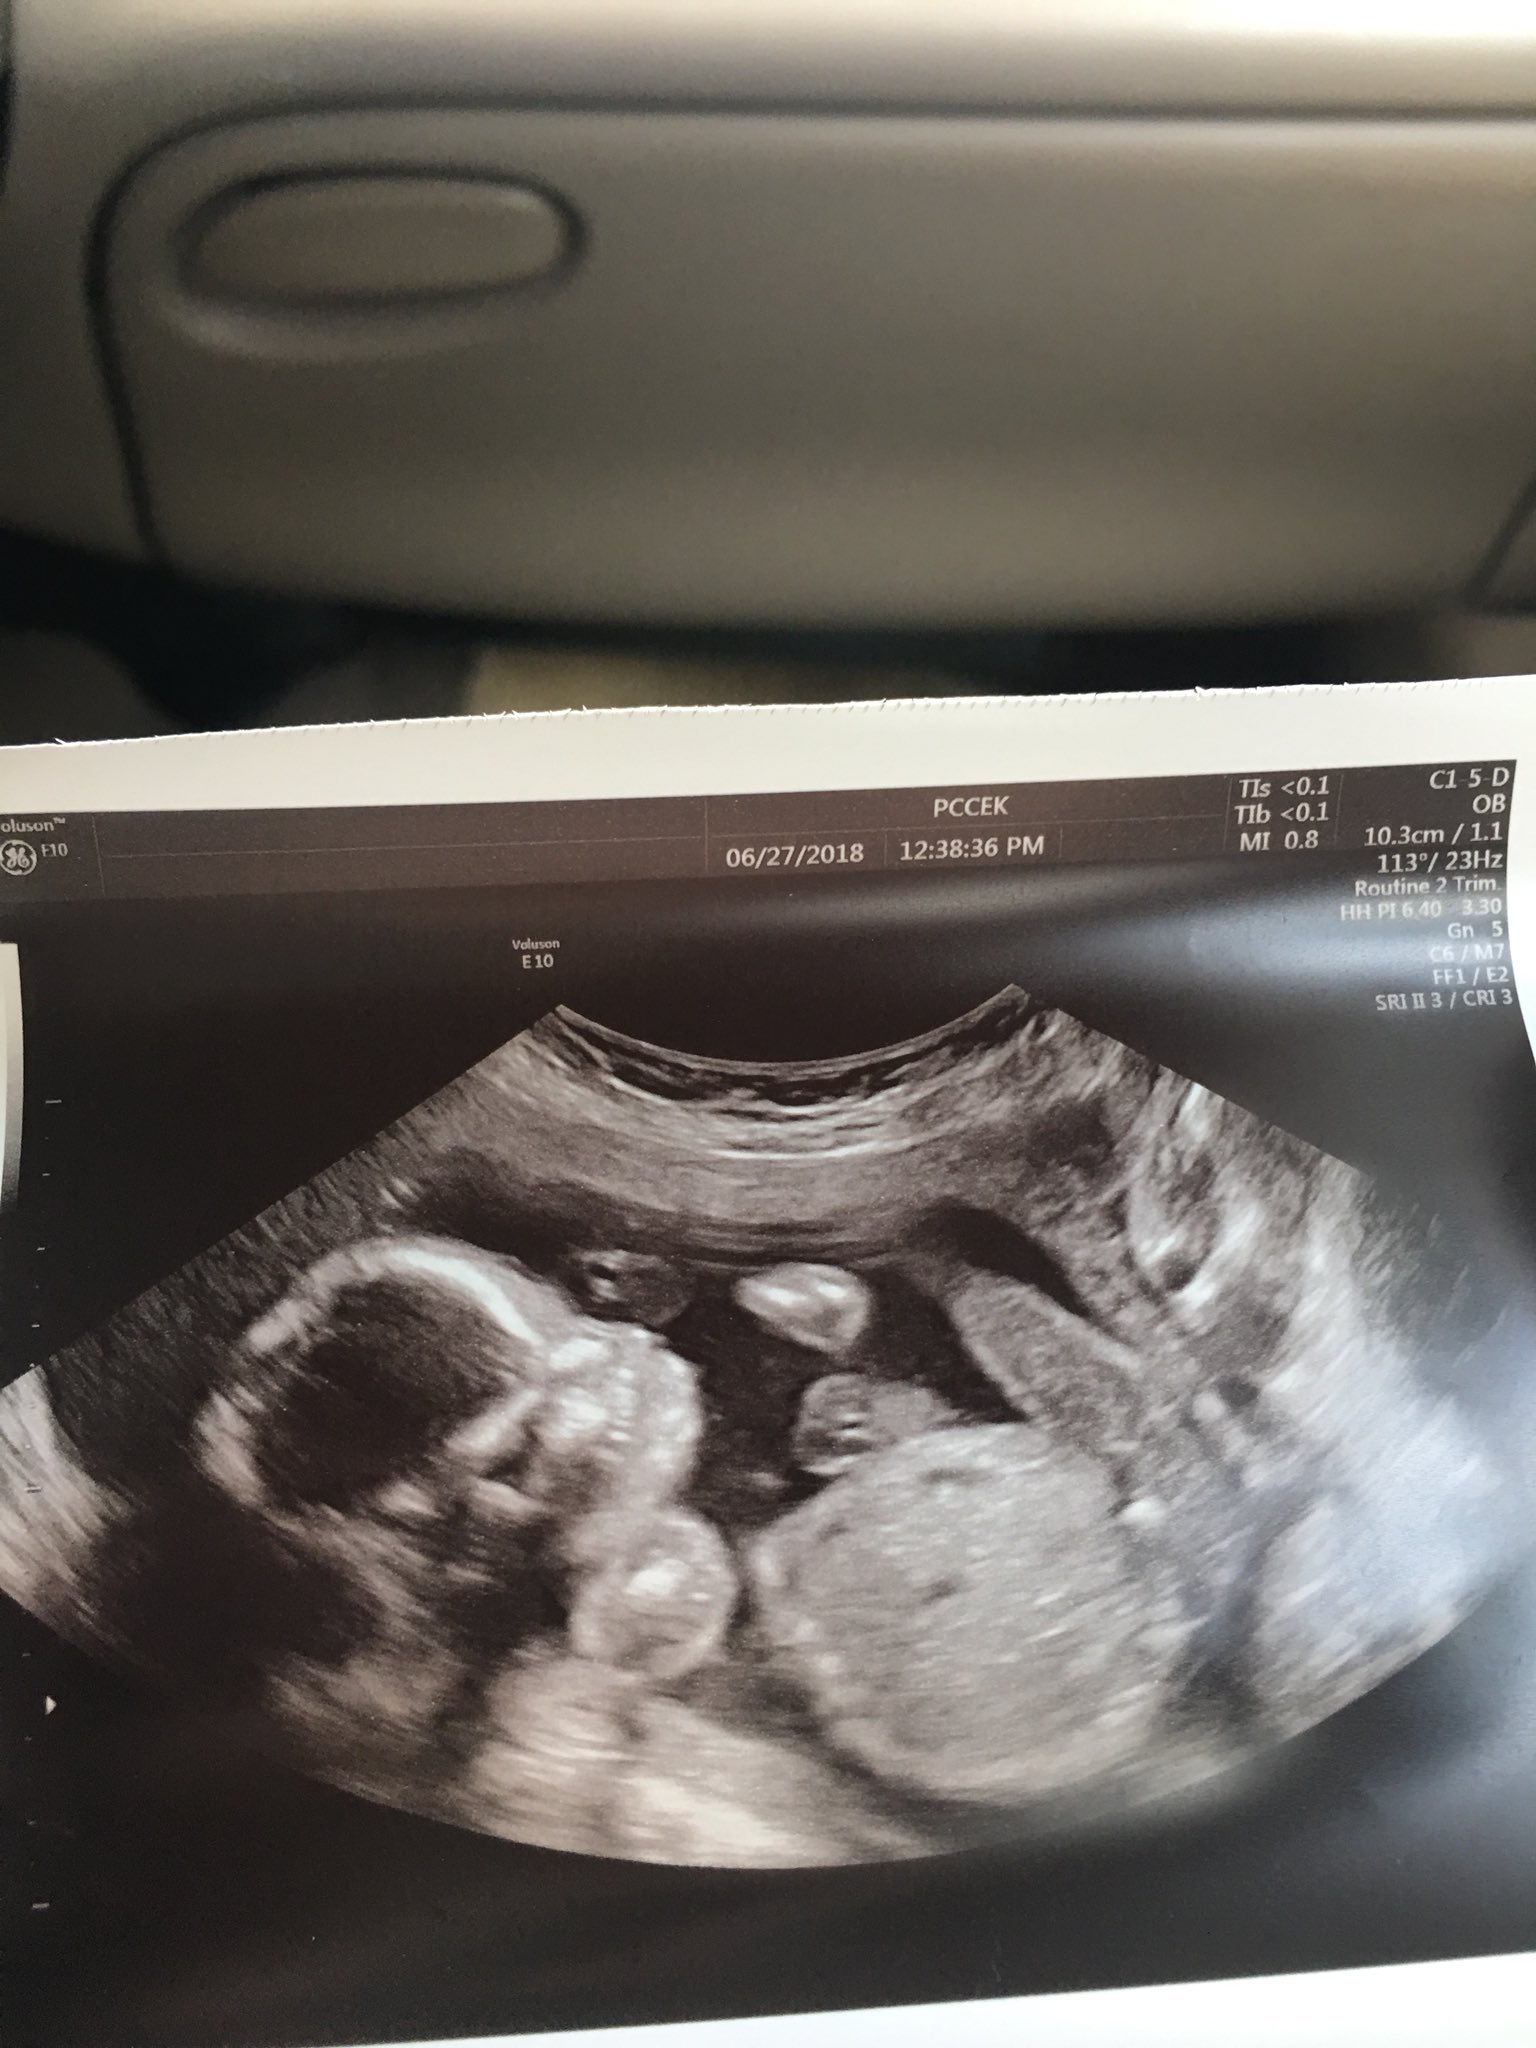

Web Beginning of pregnancy. Baby boy at delivery he was born at 35 weeks. Everything looks great and baby Ruby is in the 59 for weight.

A healthy resting heart rate can vary by age. Web I am almost 35 weeks along FTM and had a ultrasound to check growth. The babys heart rate was up in the 180s.